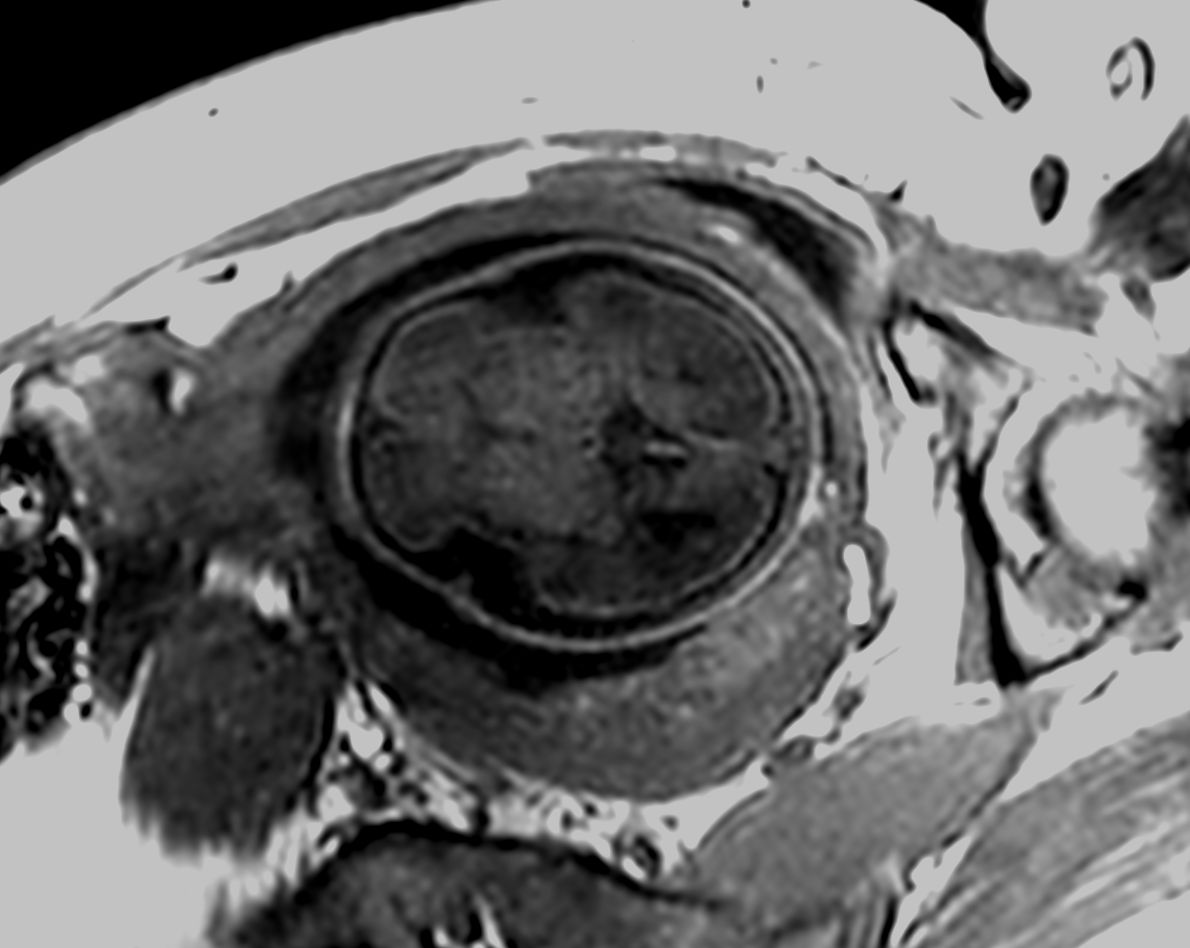

Pregnant patient, referred to MRI for fetal brain and spine imaging.

Axial T2w FLAIRCompressed SENSE